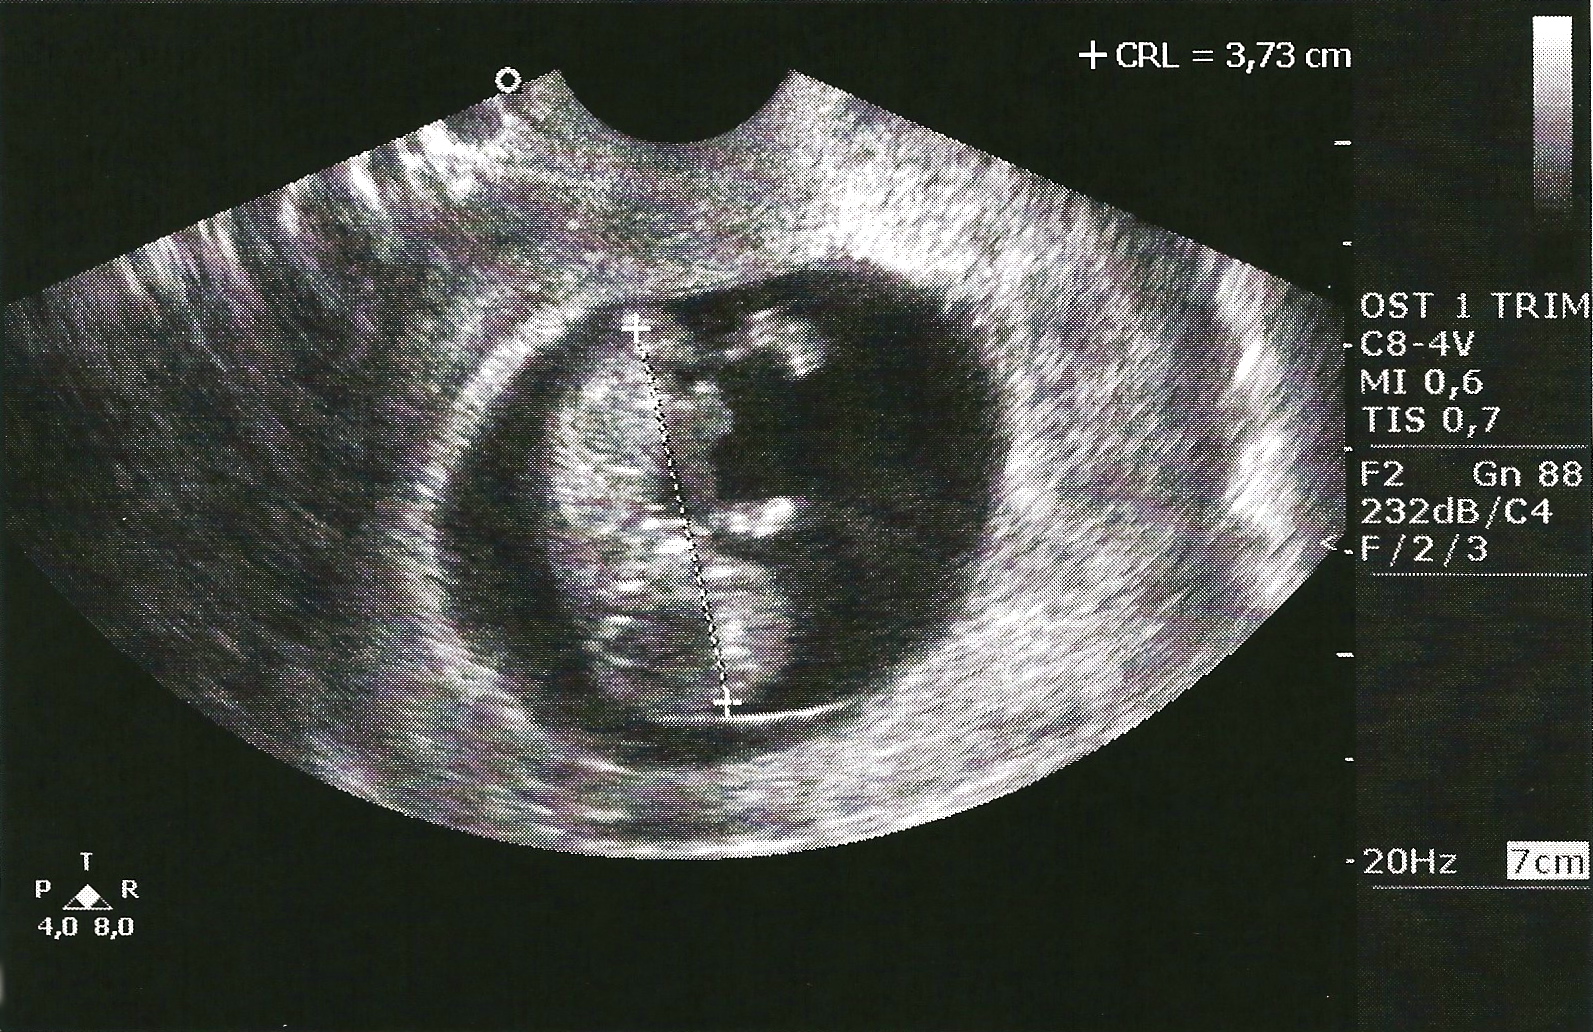

Today we saw our baby for the first time! It was incredible. It seemed like one second I was settling into the chair and the next I was gazing at this human being inside of me! The words the technician was uttering in Italian describing what we were seeing (while our friend did her best to keep up with translation), almost faded to the background as I was mesmerized by what I saw. We saw the little bursts of energy that represented the heartbeat and I felt a wave of relief as our pregnancy went from surreal to real.

Just as I was getting used to this new reality, I saw one of the most amazing things I’ve ever seen. Our baby started kicking for us. With that sight my newfound joy finally found my face and I couldn’t stop smiling as I watched. How incredible is it that after 10 weeks God has already knitted our unborn child together in such intricate ways. It is less than a couple inches long and yet he or she has fingers and toes, functioning organs, and peach fuzz hair on his or her precious skin. What a crazy privilege to be carrying this child who is being fearfully and wonderfully made (Psalm 139)!

And now I proudly present to you, the first pictures of our baby!